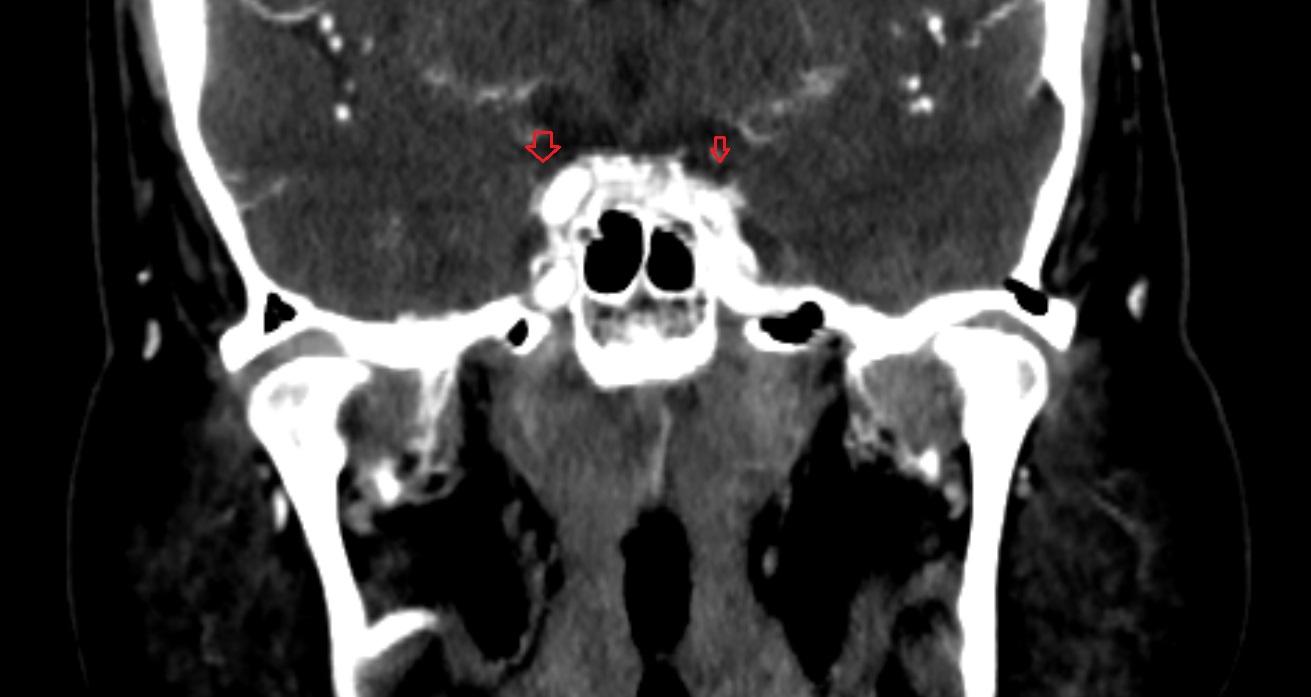

- Hippocampus